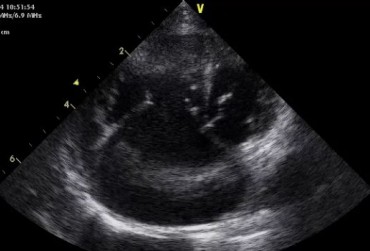

Zwężenie zastawki trójdzielnej jest jedną z form dysplazji pojawiającą się w różnym stopniu nasilenia (najczęściej łącznie z niedomykalnością zastawki) zarówno u psów, jak i u kotów. Cechami charakterystycznymi definiującymi zwężenie zastawki trójdzielnej są: obecność rozkurczowego wybrzuszenia (doming) płatków zastawki, zmniejszona ruchomość płatków, zmniejszona średnica ujścia zastawki. Mimo że zmiany morfologiczne aparatu trójdzielnego są typowe w przebiegu TVD i są znakiem rozpoznawczym tej choroby, nie są one zawsze bardzo silnie wyrażone i nie zawsze można mieć bezsprzeczną pewność diagnostyczną, bazując na badaniu echokardiograficznym [10]. Przypadki takie zdarzają się przede wszystkim u pacjentów, u których nie postawiono diagnozy we wczesnym etapie życia, a którzy pojawiają się na badaniu dopiero w starszym wieku z zaawansowanymi zmianami i niejednokrotnie z klinicznymi objawami prawostronnej niewydolności mięśnia sercowego i towarzyszącymi zaburzeniami w rytmie. W takich przypadkach obraz choroby może przypominać arytmogenną kardiomiopatię prawokomorową (arrhythmogenic right ventricular cardiomyopathy – ARVC) [1, 8]. Preekscytacja jest często obserwowana u ludzi z anomalią Ebsteina. U zwierzat, podobnie jak u ludzi, obecność dodatkowej drogi przewodzenia może nigdy nie prowadzić do rozwoju tachykardii nadkomorowej lub arytmia ta pojawiać się może dopiero w późniejszym okresie życia. Opisany przypadek jest przykładem pacjenta z dysplazją zastawki trójdzielnej i prawostronną niewydolnością serca będącą najprawdopodobniej konsekwencją tachykardii nadkomorowej.